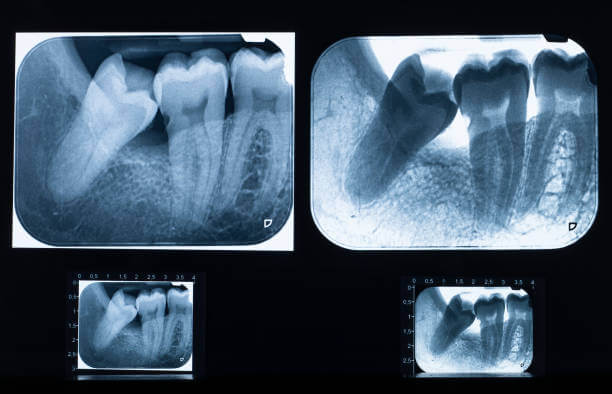

- 정밀 진단 – 3D CT·X-ray 촬영

- 이식 계획 수립 – 치근·수용부 적합성 확인